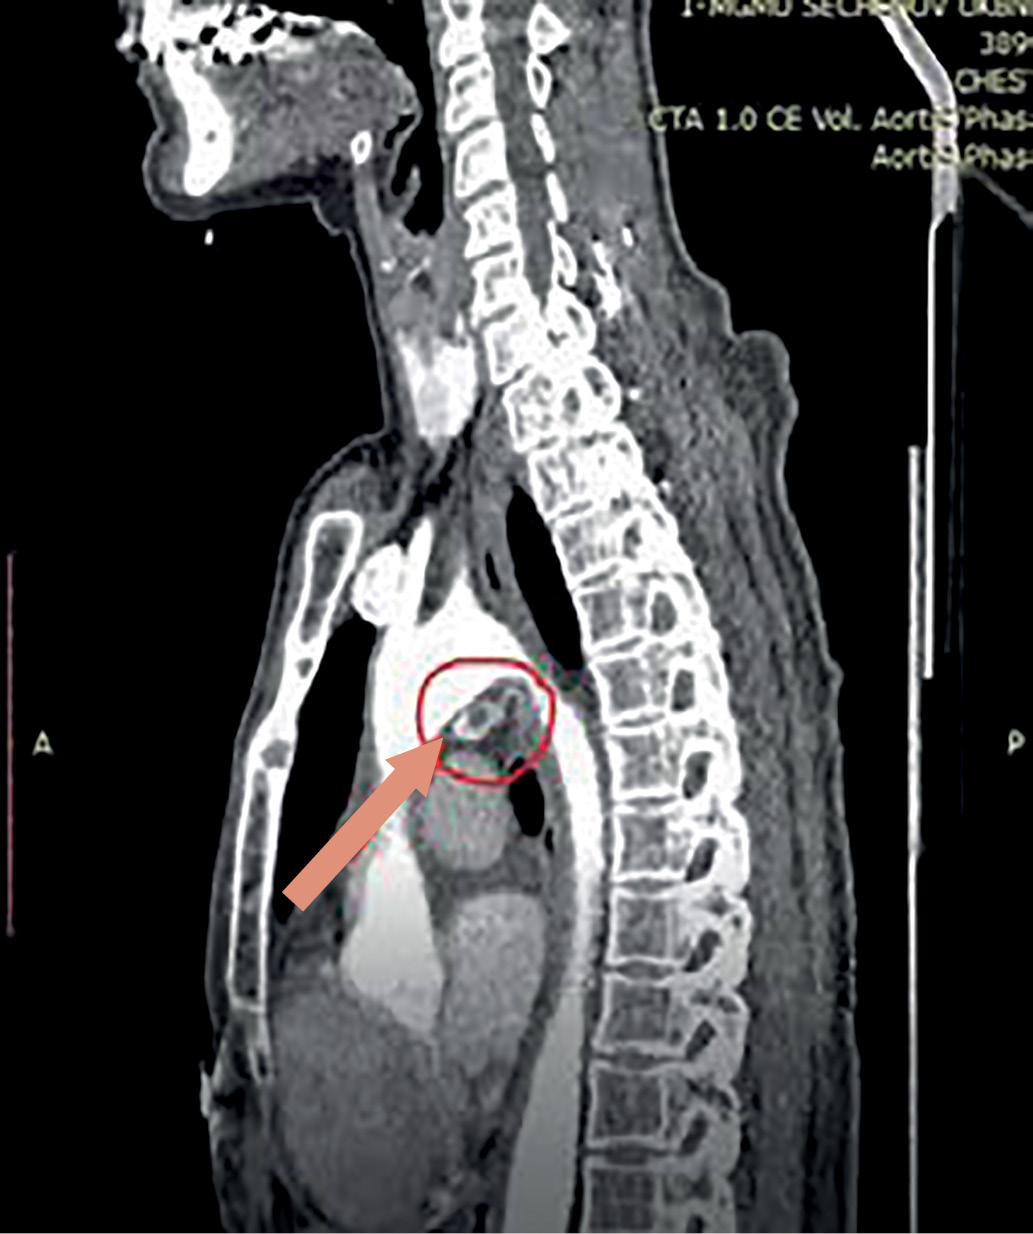

4. Рисунок 4. Томограмма, сагиттальная проекция. Новообразование ОЩЖ указано стрелкой. | |